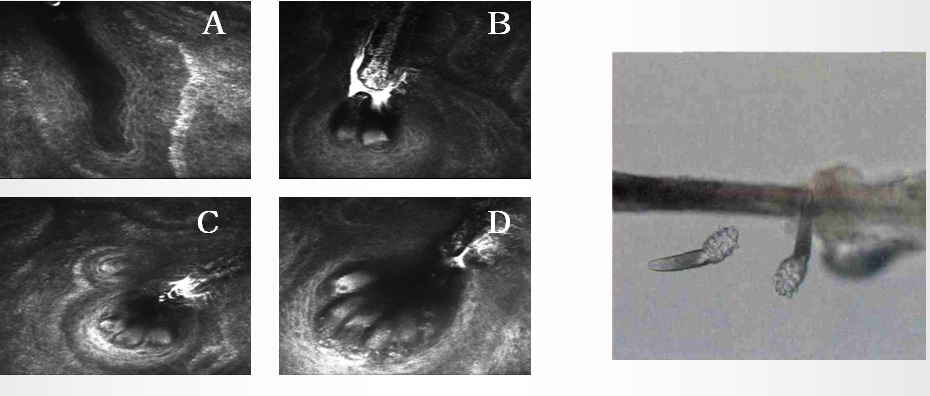

睑板腺形态(包括数量及分泌物)的改变是评价睑板腺功能的客观依据。目前,用于观察和分析睑板腺形态学的方法主要包括裂隙灯检查、睑板腺红外照相仪和活体共聚焦显微镜技术。裂隙灯检查能够观察睑缘的形态、睑板腺的分泌状态、角结膜的状况以及泪河的高度等。睑板腺由于其丰富的酯质颗粒,在受到红外线照射时会产生散射光线,这一特性使得红外线透照技术成为早期用于观察睑板腺形态学的有效手段。活体共聚焦显微镜技术则提供了更为精细的观察能力,它能够精确地观察到细胞层面,从而在活体状态下分析睑板腺在正常和病理条件下的微观结构变化。此外,该技术还能够清晰地观察到蠕形螨的特征性形态学结构,并对其进行计数。

图片

近期的研究表明,眼部蠕形螨感染可能是导致睑板腺功能障碍(MGD)的一个潜在危险因素。然而,传统的拔睫毛镜检法在检测蠕形螨感染方面存在一定的局限性,这促使医学界寻求更为精确和有效的诊断方法。张明昌教授团队进行了一项相关研究,研究显示,MGD患者的睑板腺微观结构指标均比对照组差。蠕形螨(+)患者睑板腺微观结构指标比蠕形螨(-)患者差,睑板腺微观结构的损伤与眼部蠕形螨感染的数量呈正相关。这项研究为蠕形螨的检测提供了更微创、有效的手段。